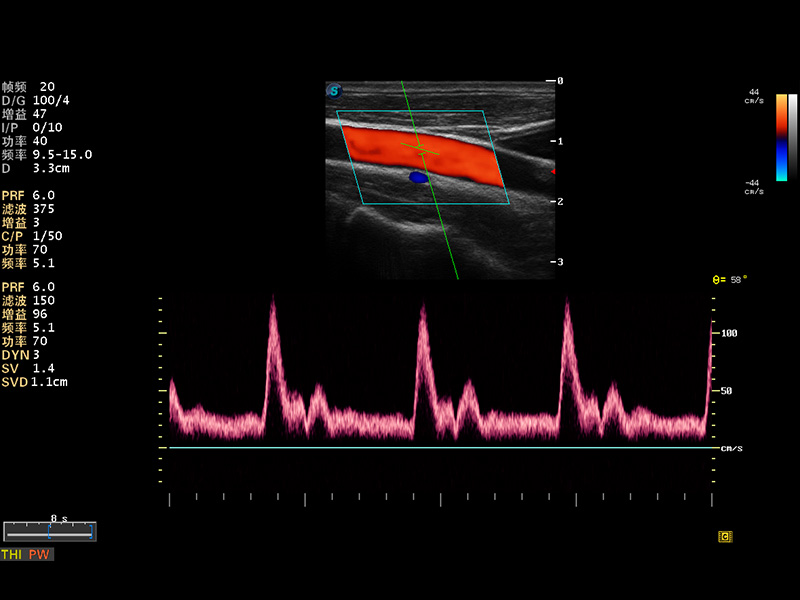

S8 EXP便携式彩色多普勒超声诊断仪是狗万官方网站研发的高端全身应用型便携彩超。高通道的VIS平台融合可视化(Visual)、智能化(Intelligent)和人性化(Smart)的特点,配以狗万官方网站自主研发生产的探头大家族,使您能够快速、准确的获得病人信息,提高工作效率的同时减轻疲劳。

成像技术

多波束形成器